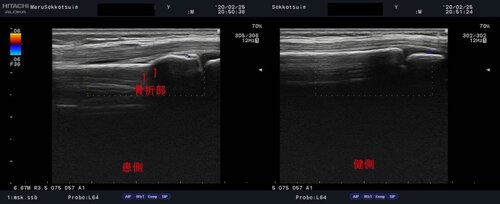

10歳 男児 サッカープレイヤー

サッカーの練習中、コーチが蹴ったボールが右手首付近に強打し受傷。

来院時は腕の中央が痛いと訴えておりましたが、

しっかり問診、視診、触診を行い、確認の為、エコー検査をした所、

橈骨遠位端、骨端線より近位に骨折様のエコー像を確認。

「橈骨遠位端部骨折」ですね。

なかなかの強いボールがヒットした模様です。。。

今回は骨端線という成長軟骨から少し肘よりの骨折で、

成長障害の心配は少ないですが、まずはしっかりと固定をして、